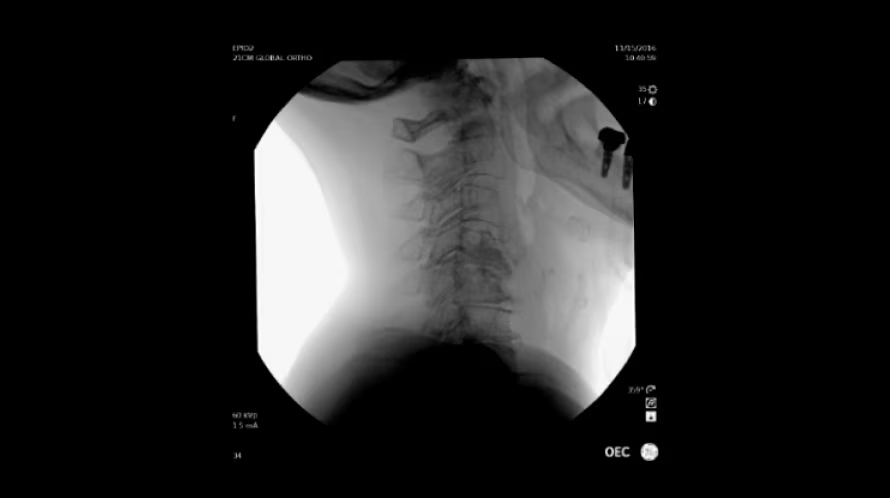

GE OEC Elite CFD относится к мобильным рентгенохирургическим системам премиум-уровня и предназначена для проведения интраоперационных рентгеноскопических и рентгенографических исследований в хирургии, травматологии, ортопедии, сосудистых и эндоваскулярных вмешательствах, нейрохирургии и урологии. Плоскопанельный КМОП-детектор с полем обзора 21×21 см, высоким динамическим диапазоном и частотой до 30 кадров/с обеспечивает детализированную визуализацию костных структур, мягких тканей и контрастированных сосудов в режиме реального времени. Передача изображения 1:1 на 32-дюймовый 4K-монитор просмотровой станции позволяет хирургу уверенно ориентироваться в операционном поле, контролировать положение инструментов и имплантов, минимизируя количество повторных экспозиций.

Интеллектуальные профили обработки изображения и несколько режимов контроля дозы помогают адаптировать параметры системы под клиническую задачу и анатомию пациента. Мобильная С-дуга GE OEC Elite CFD доступна с различными вариантами штатива (Ergo C, Super C, моторизованный Super C), что расширяет возможности позиционирования при работе в ограниченном пространстве операционной. Сенсорная панель управления, функции LiveZoom, специализированные сосудистые и кардиологические профили, а также интеграция с PACS и информационными системами делают комплекс удобным инструментом для потоковой интраоперационной визуализации, повышая эффективность работы операционной бригады и качество рентгенологических исследований.

- Маневренный штатив С-дуги с глубиной дуги ≈84 см и широким диапазоном орбитального и поперечного вращения для сложных проекций.

| Глубина С-дуги | ≈84 см |

| Диапазон орбитального вращения | +55° / −90° |

| Поперечное вращение С-дуги | 360° (90° / 270°) |